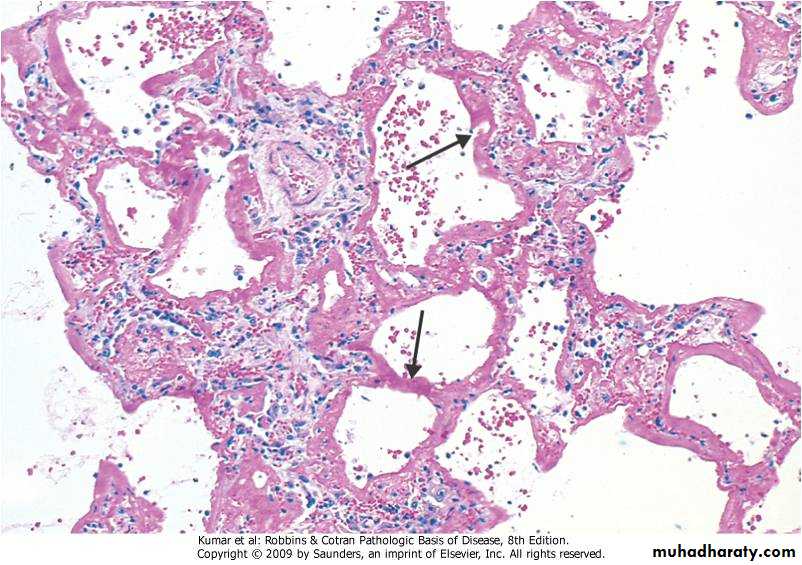

Micro:

Diffuse alveolar wall damage( epithelial & endothelial)

Alveolar wall is lined by hyaline materials Latter on intra alveolar organization takes place